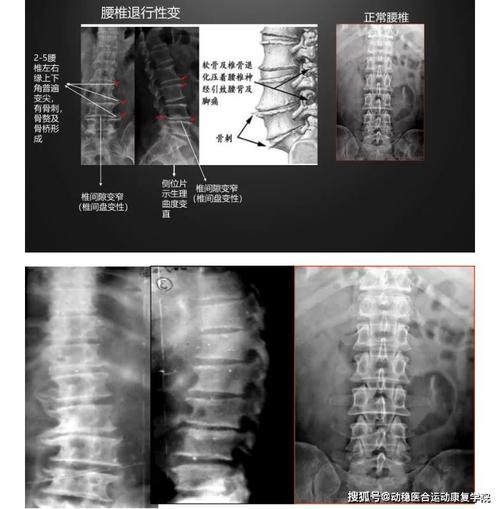

腰痛常见原因——腰椎退行性变的x线片阅读

腰痛常见原因腰椎退行性变的x线片阅读